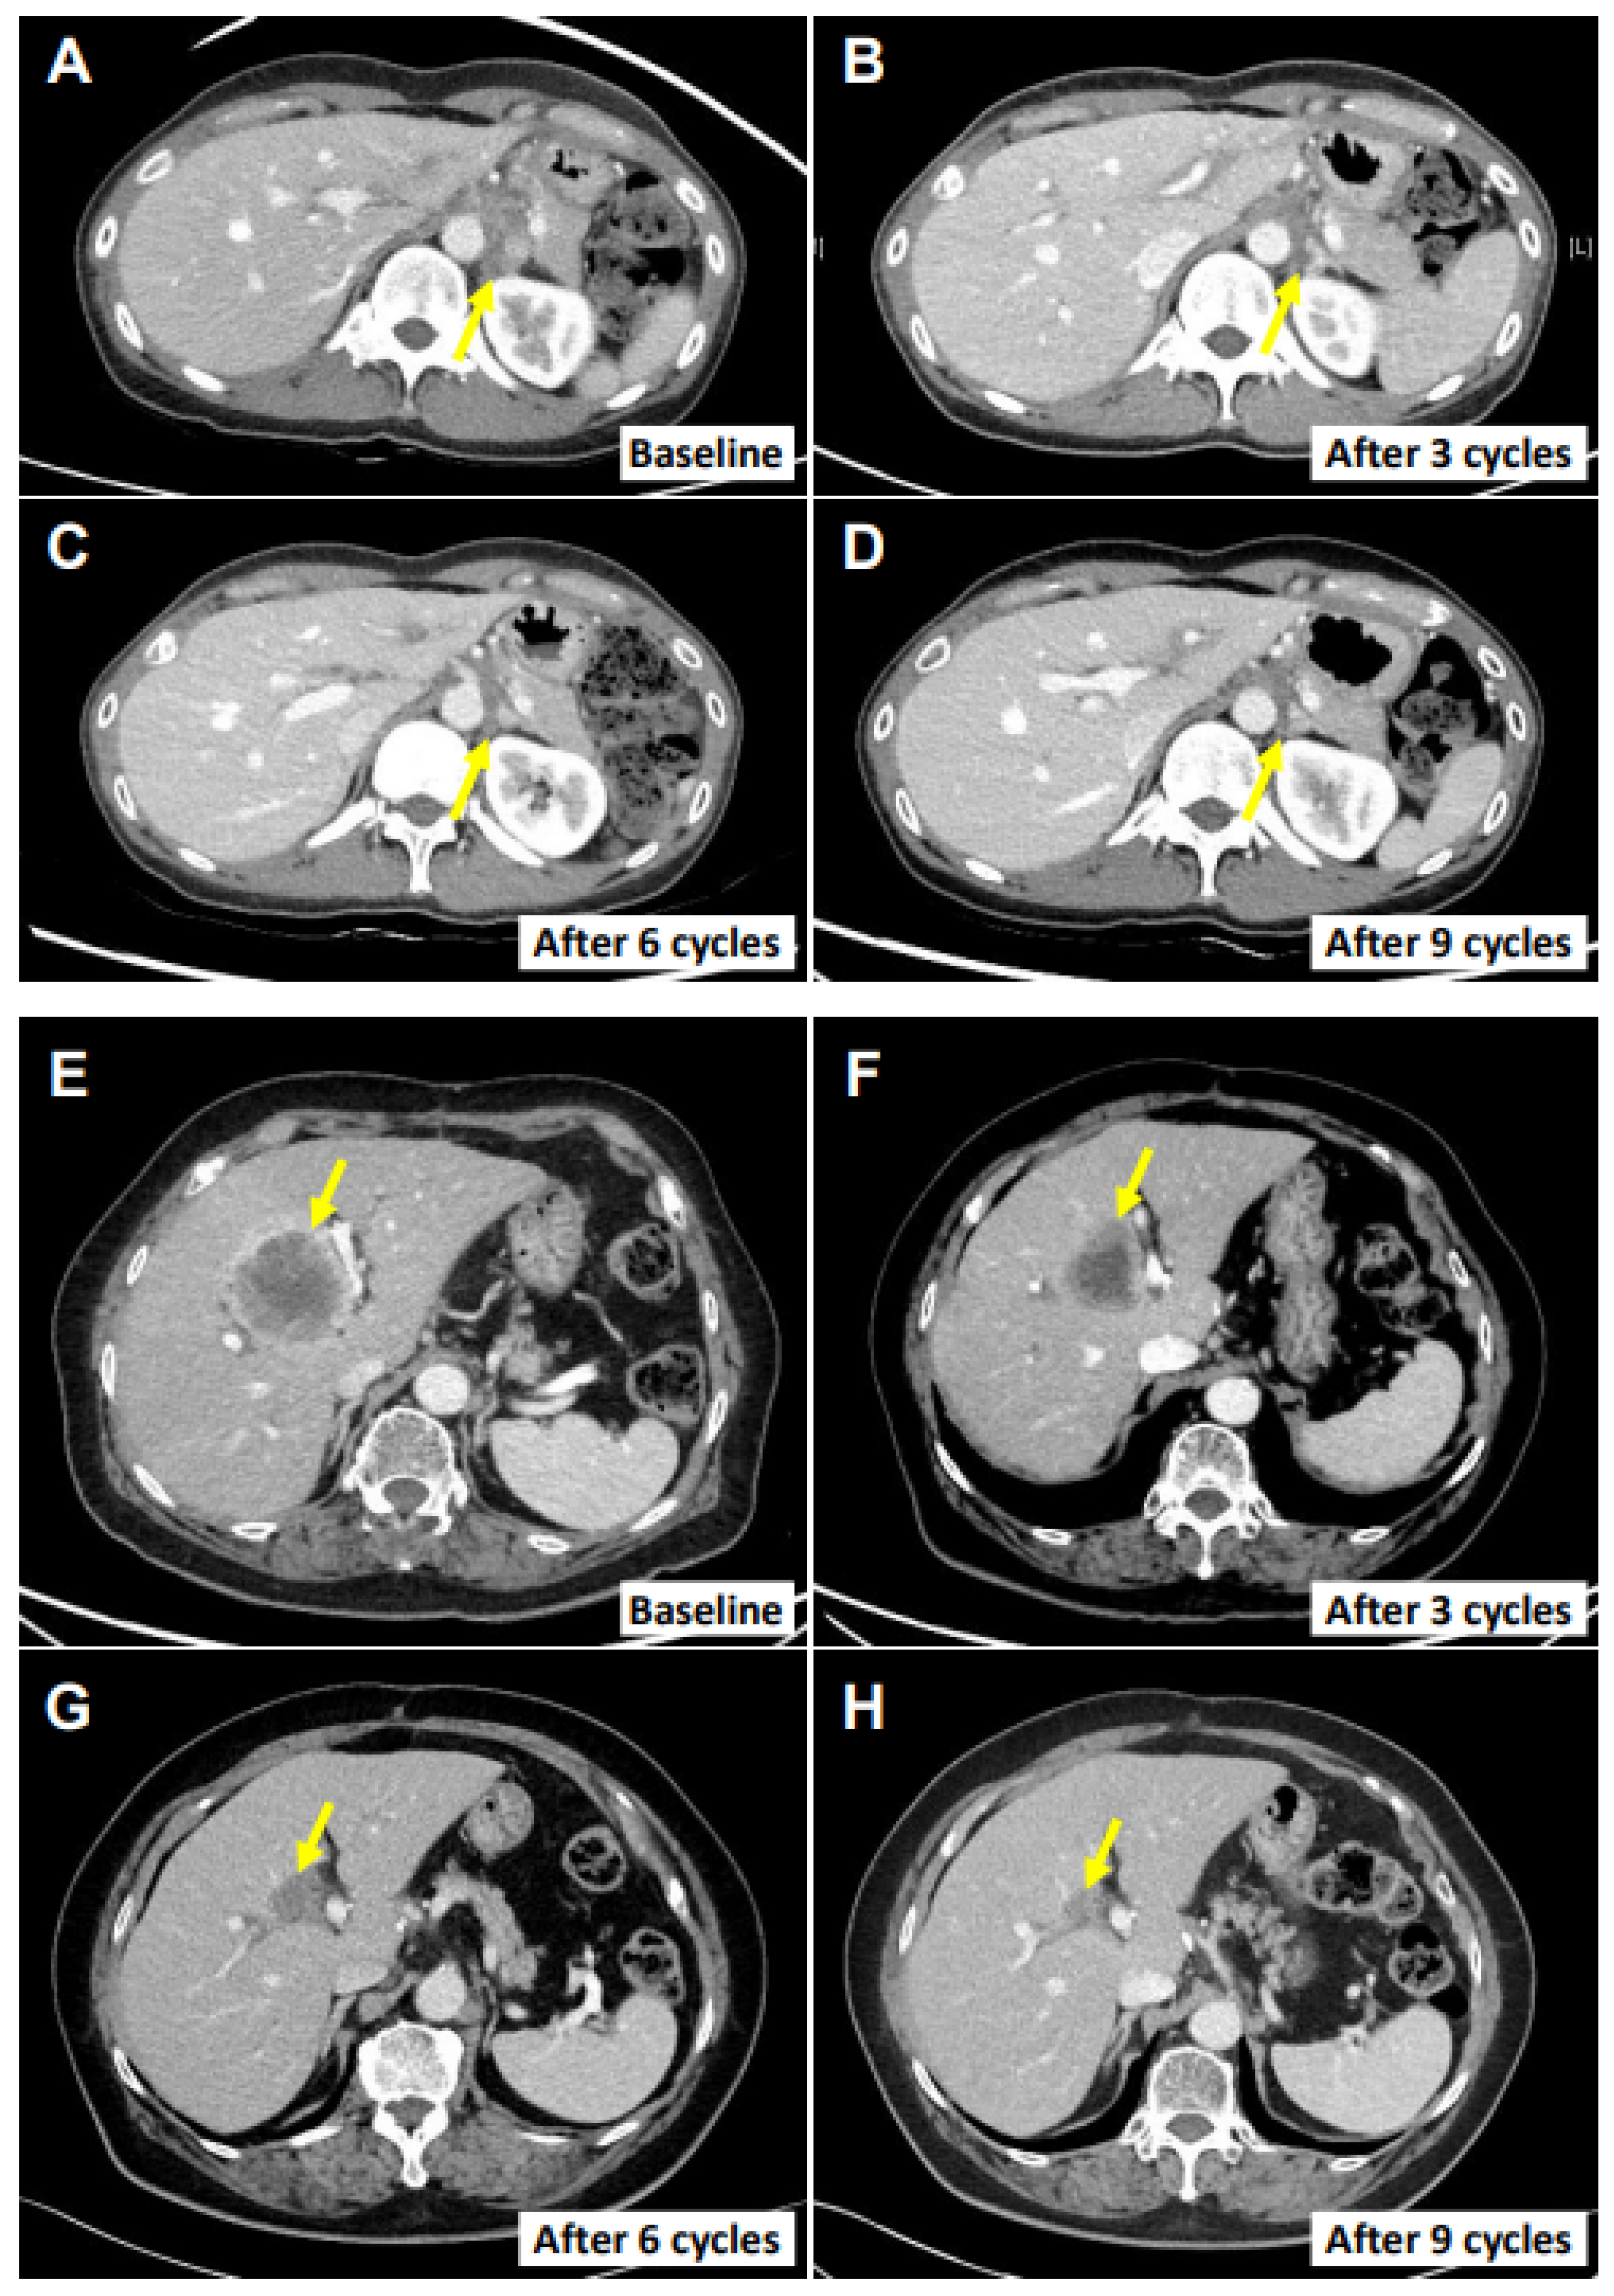

Figure 3.

Cancer regression in two patients. CT images of the main tumor lesions at the baseline in each response evaluation. (A–D) Left infrarenal lymph node in patient E0107. (E–H) The main hepatic metastasis lesion in patient E0217. Yellow arrows indicate the target lesions. Response evaluations were performed after every three cycles.

The ORR (CR and PR) at the end of the study protocol was 17.4% (95% CI, 5.0–38.8%) in the full analysis set and 50.0% (95% CI, 15.7–84.3%) in the per-protocol set. The DCR (CR, PR, and SD) at the end of the study protocol was 30.4% (95% CI, 13.9–54.9%) in the full analysis set and 62.5% (95% CI, 24.5–91.5%) in the per-protocol set (Table 1). There was no significant difference in the ORR according to the CPS (Table S4). When considering the best responses of each patient, the DCR was up to 73.9%, and the maximal change in the targeted lesions from the baseline was −82.3% to 169% (Figure 2). Importantly, two patients demonstrated the sustained objective regression of their main targeted lesions, as assessed by RECIST. Patient E0107, a 40-year-old female diagnosed with gallbladder cancer with peritoneal carcinomatosis after undergoing cholecystectomy due to cholecystitis, had previously received chemotherapies including gemcitabine, cisplatin, 5-fluorouracil (5-FU), onivyde® (irinotecan liposome), and leucovorin. After treatment with SMT-NKs and pembrolizumab as described above, she experienced an 82.3% reduction in the metastatic lymph nodes (Figure 3A–D) and remained progression-free 18 months after the initial treatment. Patient E0217, a 76-year-old female diagnosed with extrahepatic cholangiocarcinoma, underwent surgery for the segmental resection of the common bile duct and cholecystectomy. Four months later, several hepatic metastases were found, and she received systemic chemotherapy with gemcitabine and cisplatin. The multiple hepatic lesions then progressed. After the SMT-NK and pembrolizumab treatment as described above, she experienced a 70.4% reduction in the hepatic metastasis lesions (Figure 3E–H) and remained free from progression 12 months after the initial treatment. At the time of analysis, the median PFS was 4.1 months (95% CI, 1.8–5.9 months) in the full analysis set (Figure 4). As the progression rate was less than 50%, the median PFS in the per-protocol set could not be calculated. We found no significant difference in the PFS according to the CPS (Table S5). The mortality rate was less than 50% in both sets, so the median overall survival could not be estimated in any set.